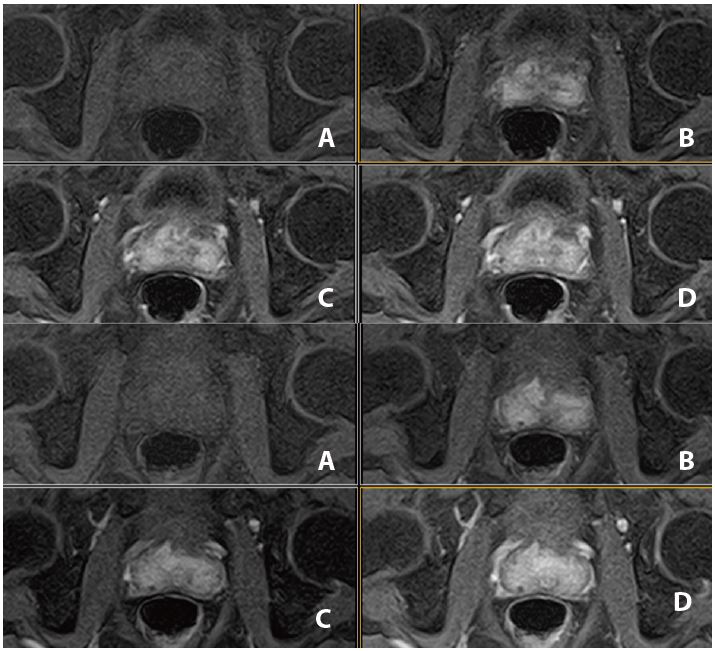

Рис. 2. Аксіальне, Т2-зважене зображення (за протоколом mpMR).

Рис. 3. Аксиальне DWI – A=b0, B=Iso b800, C=Iso b1000 e, D=Iso ADC (за протоколом mpMR)

Рис. 6. Аксіальне, Т2-зважене зображне (за протоколом mpMR).

Рис. 7. Аксіальне DWI – A=b0, B=Iso b800, C=Iso b1000 e, D=Iso ADC (за протоколом mpMR)

Рис. 10. Аксіальне, Т2-зважене зображення (за протоколом mpMR).

Рис. 11. Аксіальне DWI – A=b0, B=Iso b800, C=Iso b1000 e, D=Iso ADC (за протоколом mpMR).

Рис. 14. Аксіальне, Т2-зважене зображне (за протоколом mpMR).

Рис. 15. Aксіальне DWI – A=b0, B=Iso b800, C=Iso b1000 e, D=Iso ADC (за протоколом mpMR)